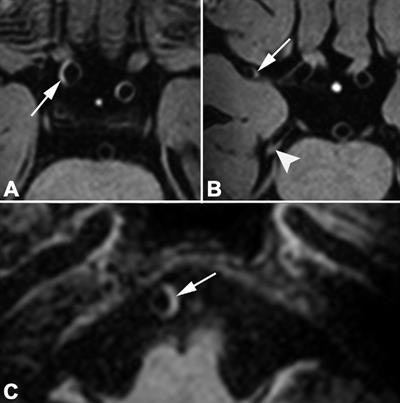

Risk factors such as hypertension, diabetes, and smoking have been associated with intracranial atherosclerosis, which accounts for 5% to 23% of ischemic strokes in the white population. While CT and MR angiography or digital subtraction angiography have been used to determine a link between intracranial calcifications, stenoses, and ischemic stroke, the modalities are limited in the evaluation of vessel wall lesions, which occur at the most advanced stage of intracranial atherosclerosis. Therefore, 3- and 7-tesla MRI have become increasingly utilized to detect the anomalies more expeditiously.

The question remains, however, as to which cardiovascular risk factors are the greatest contributors to vessel wall narrowing. In this study, Lindenholz and colleagues explored age, hypertension, gender, high or low levels of fat and lipids in the blood, and other influencers and their relationships to vessel wall lesions (Radiology, April 2020, Vol. 295:1, pp. 162-170).